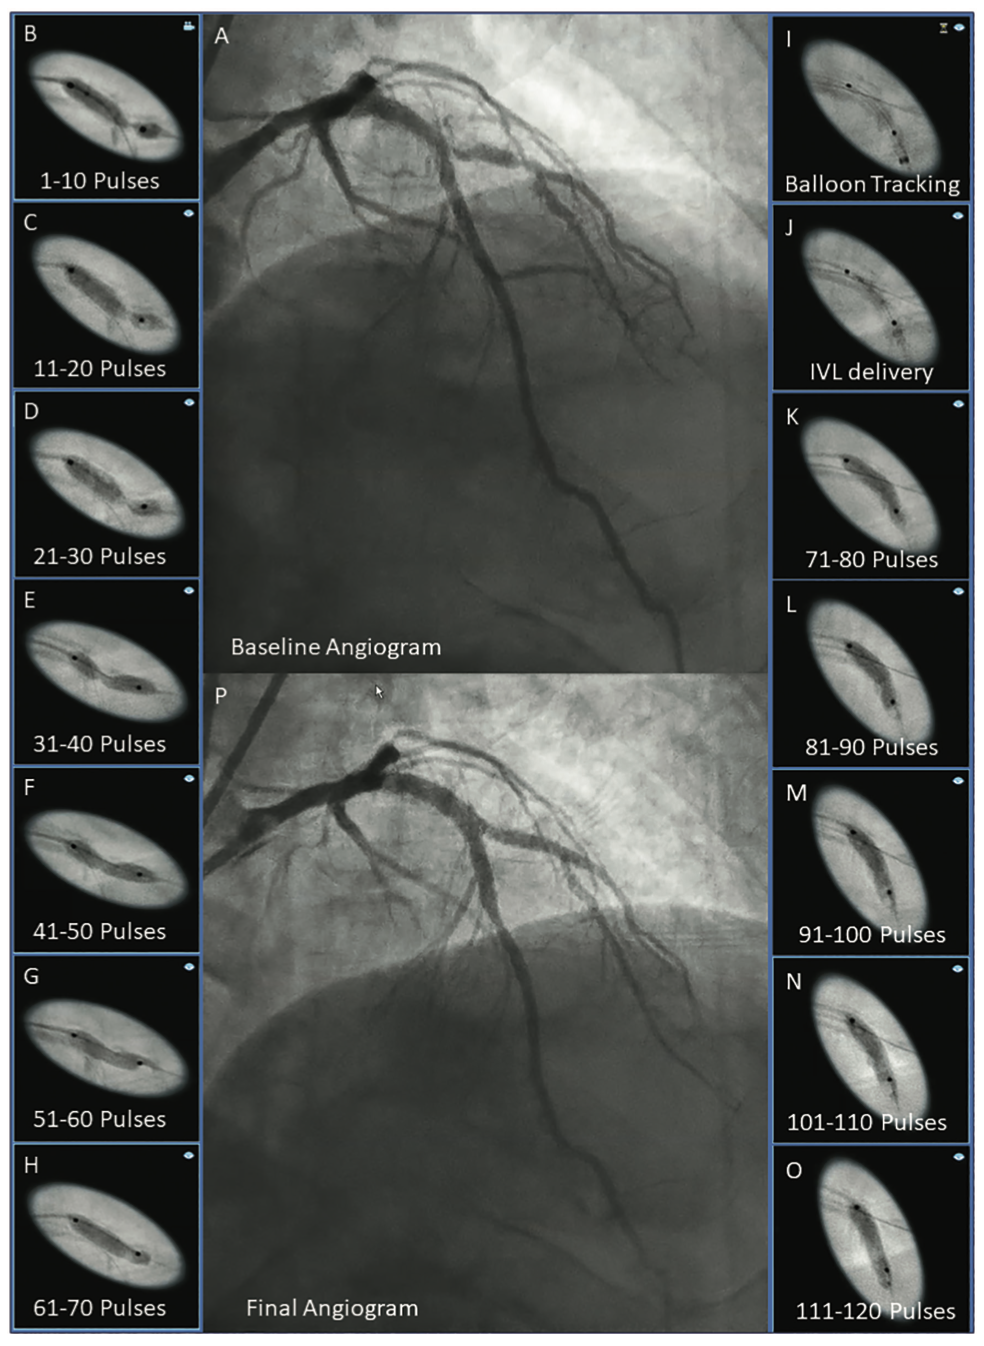

No, the ability to use 120 pulses has essentially eliminated that. In fact, we will often use one C2+ in two different vessels. Yesterday we had a severely calcified left anterior descending (LAD) and diagonal bifurcation (Figure). We delivered the C2+ to the diagonal and delivered 70 pulses into a very resistant lesion that yielded. We then removed the used balloon, and advanced a guide extension catheter into the LAD lesion using balloon-assisted tracking and delivered the remaining 50 pulses. This allowed two-vessel preparation with one catheter. Of course, the same technique could be used in two completely separate vessels like a LAD and circumflex. The key to getting the use of the residual pulses in a used balloon is delivery through a guide extension catheter.